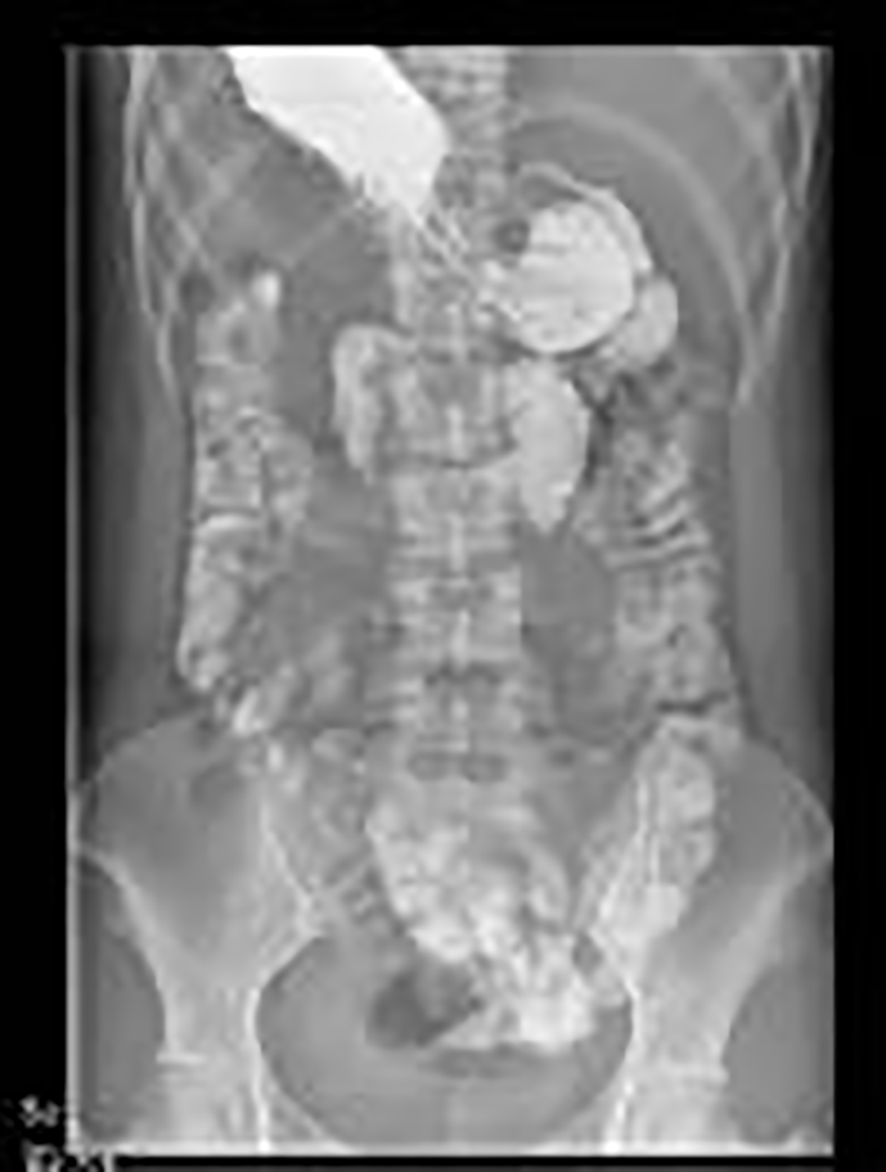

Figure 3

Followed by a gastrointestinal contrast study conducted on the 10th day post-operation, during the follow-up examination conducted 10 days postoperatively, the contrast agent was distinctly visualized traversing the ileocecal junction and subsequently entering the cecal lumen.